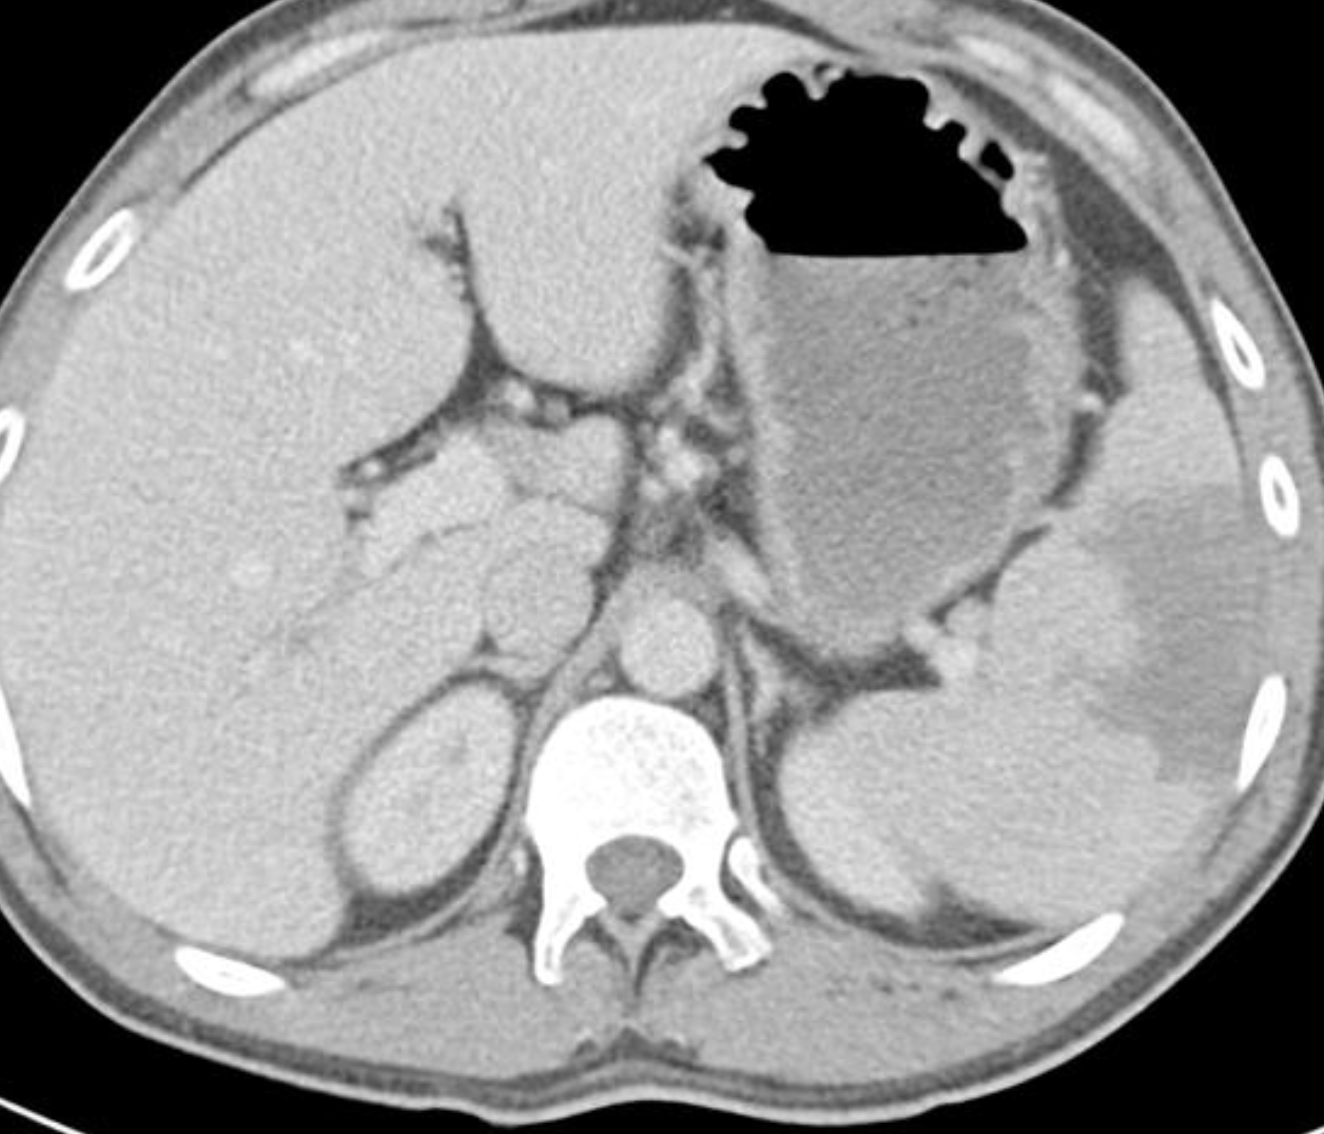

There is inversion of some abdominal structures (liver, spleen and stomach) with thoracic structures in normal position. Multiple splenules are seen on right hypochondrium. The study protocol was made for chest CT.

Case Discussion

Situs inversus partialis refers to any kind of incomplete organs inversion, like in this case. Malformations associations are more frequent in situs inversus partialis than in situs inversus totalis.